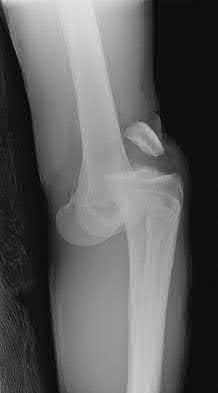

A 72-year-old woman falls down stairs and sustains the injury shown in Figure A. Additional radiographs are performed in Figure B to help assess the fracture pattern. These additional radiographs represent which of the following?

Additional traction radiographs are performed in distal humerus fractures to better understand the fracture configuration.

Traction radiographs help align the fracture fragments for better visualization. This is useful in comminuted fractures where distal fragments are telescoped or flexed on the proximal fragments, making CT scan visualization difficult.

Proper visualization can help determine (1) the approach to the distal humerus, (2) whether to perform ORIF or total elbow arthroplasty (in select patients), (3) whether to add a 3rd plate (lateral column), (4) whether to add tricortical bone graft to augment distal fixation and restore trochlear width.

Figures A and B show a distal humerus fracture without traction (A) and with traction (B) applied. Illustration A shows the same fracture after bicolumnar plating. Illustration B shows the different surgical approaches to the distal humerus (A, Campbell triceps splitting; B, O'Driscoll triceps reflecting anconeus pedicle [TRAP]; C, Bryan-Morrey triceps reflecting; D, olecranon osteotomy)